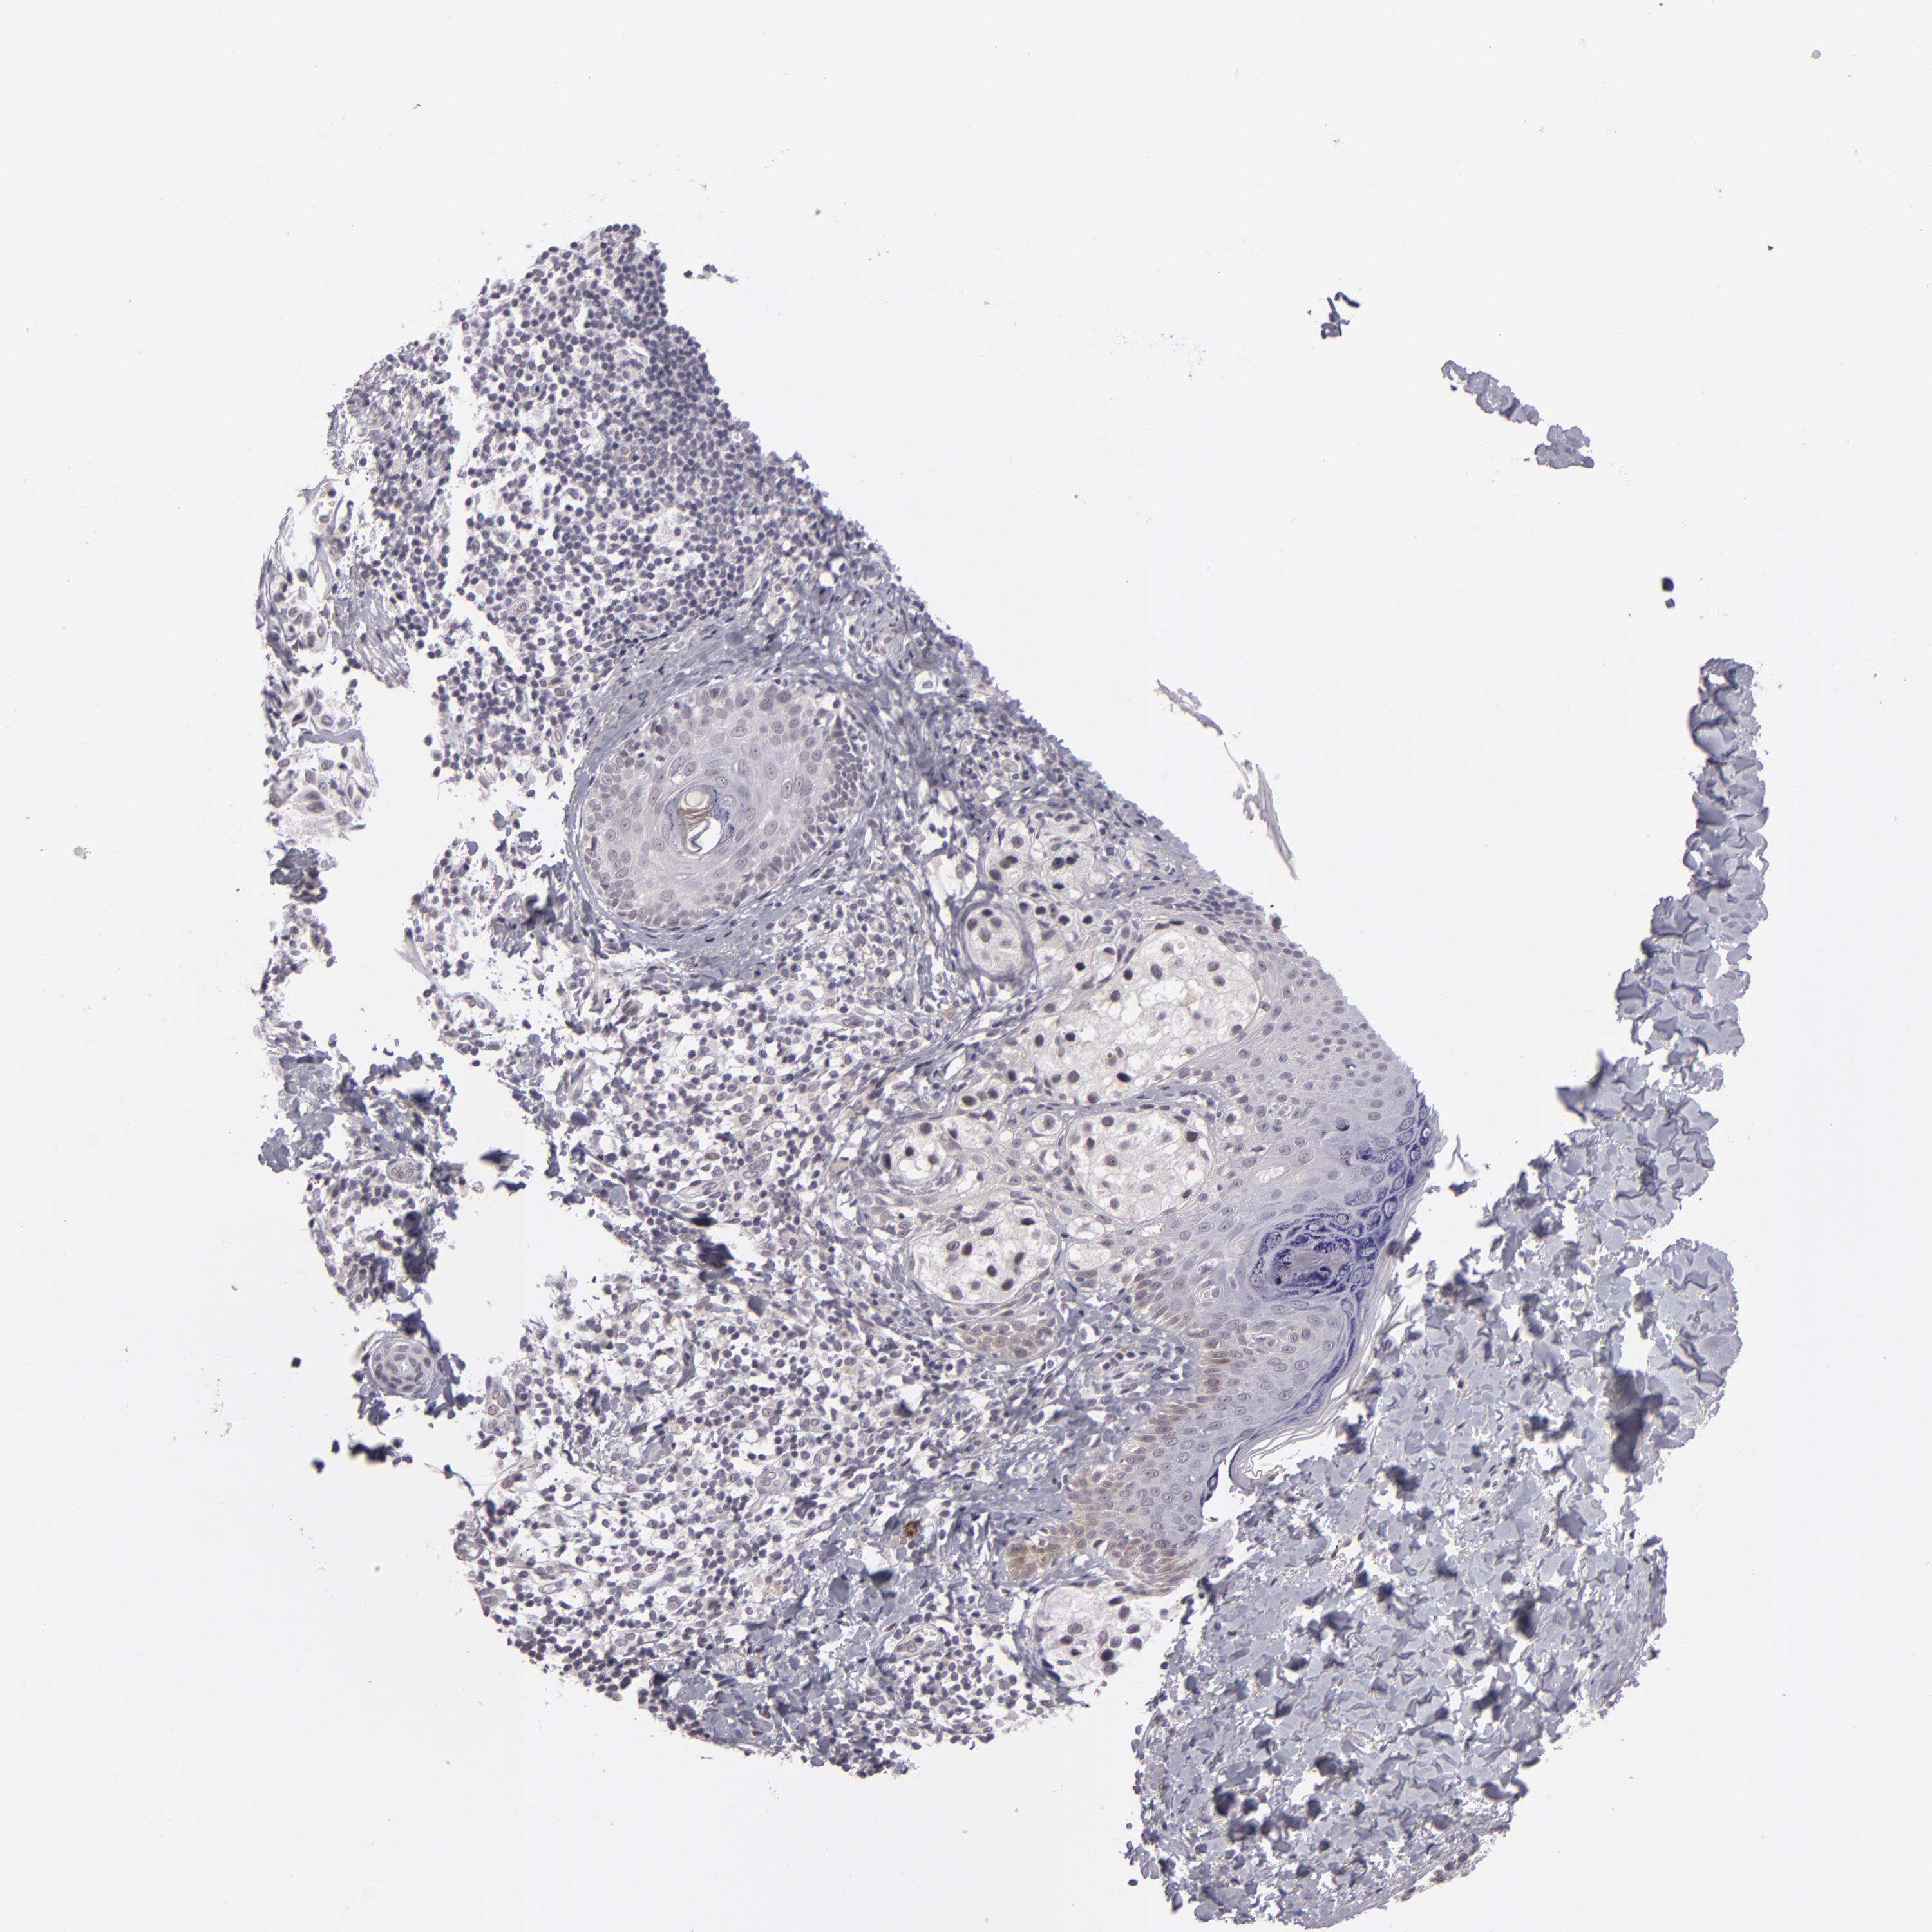

MELANOMA - Protein expressioni

A mouse-over function shows sample information and annotation data. Click on an image to view it in a full screen mode. Samples can be filtered based on level of antibody staining by selecting one or several of the following categories: high, medium, low and not detected. The assay and annotation is described here.

Note that samples used for immunohistochemistry by the Human Protein Atlas do not correspond to samples in the TCGA dataset.

Antibody stainingi

Antibody staining in the annotated cell types in the current human tissue is reported as not detected, low, medium, or high, based on conventional immunohistochemistry profiling in selected tissues. This score is based on the combination of the staining intensity and fraction of stained cells.

Each image is clickable and will lead to virtual microscopy that enables deeper exploration of all samples and also displays staining intensity scores, fraction scores and subcellular localization as well as patient and tissue information for each sample.

Antibody HPA001791

Staining

High

Medium

Low

Not detected

Intensity

Strong

Moderate

Weak

Negative

Quantity

>75%

75%-25%

<25%

None

Location

Nuclear

Cytoplasmic/membranous

Cytoplasmic/membranous,nuclear

Malignant melanoma, NOS